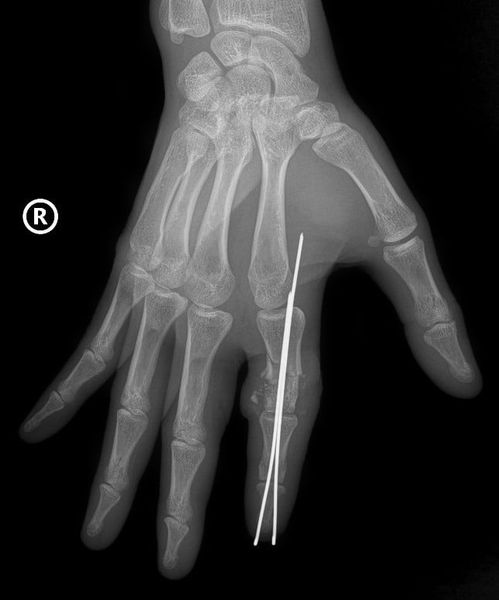

Trong phòng mổ, hai kíp phẫu thuật hoạt động song song - một kíp xử lý phần ngón đứt rời, kíp còn lại chuẩn bị phần mỏm cụt. Xương ngón được cố định bằng kim chuyên dụng để tạo trục vững; gân và dây chằng được khâu phục hồi; sau đó là bước nối thần kinh và đặc biệt nối các mạch máu nhỏ chỉ khoảng 0,8-1 mm - một công đoạn đòi hỏi độ chính xác cao dưới kính hiển vi.